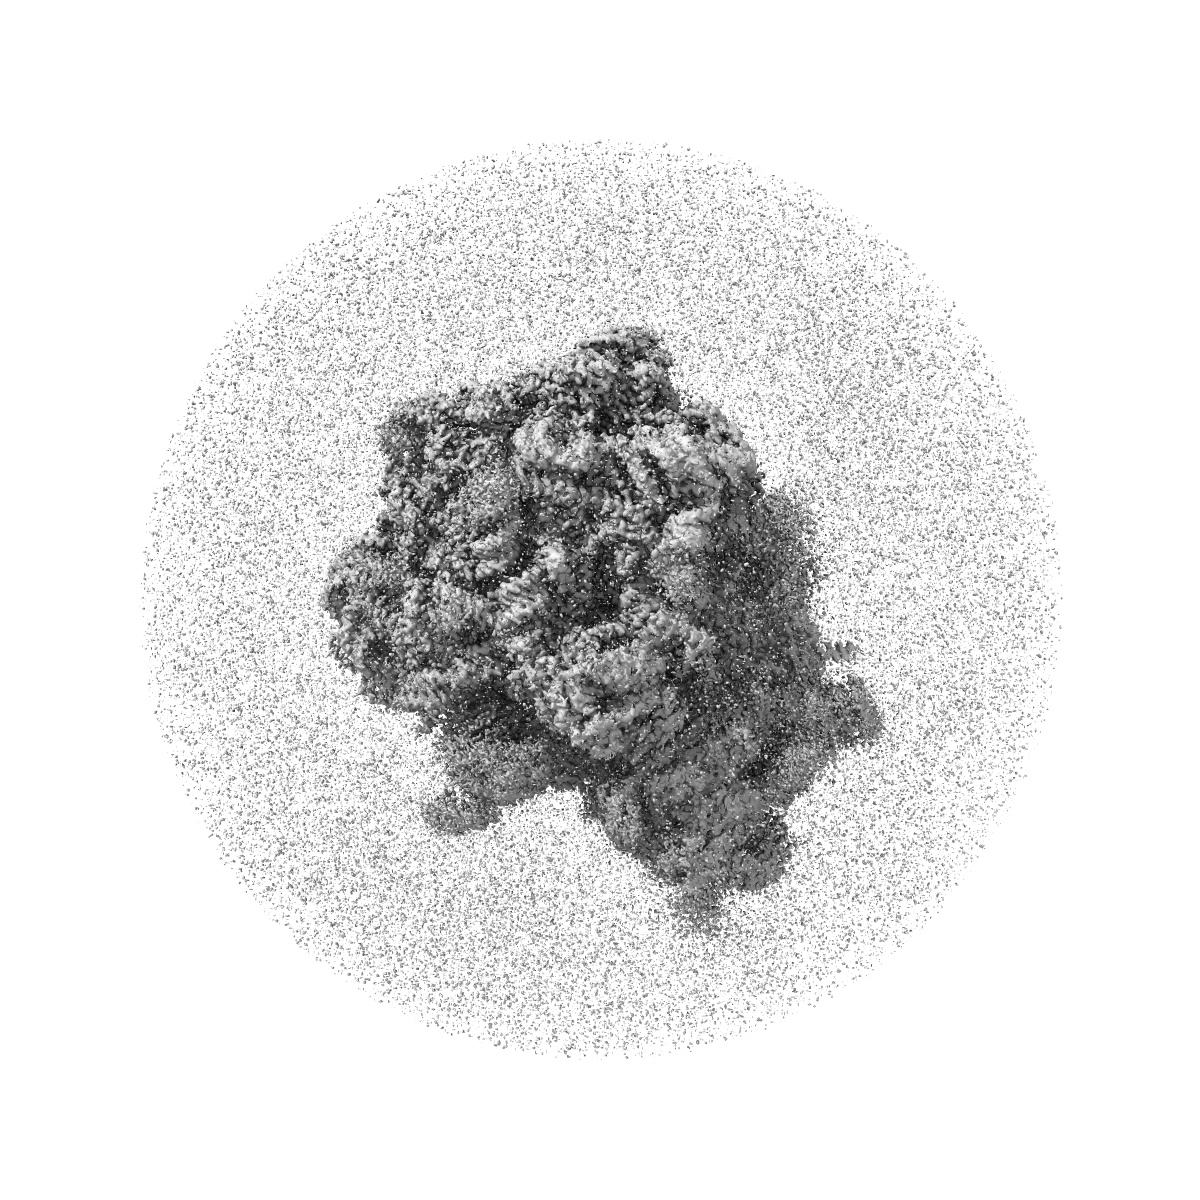

High-resolution cryo-EM structure of the Plasmodium falciparum 80S ribosome bound to E-tRNA (consensus map)

Single-particle

2.46 Å

Antimalarial drug artemisinin stabilizes PfRACK1 binding to the ribosome.

Go KD, Yan XF , Wirjanata G , Ero R, Pazicky S, Dziekan J, Tjia S, Lescar J, Bozdech Z, Gao YG

(2025) Structure , 33 , 1386 - 1397.e5